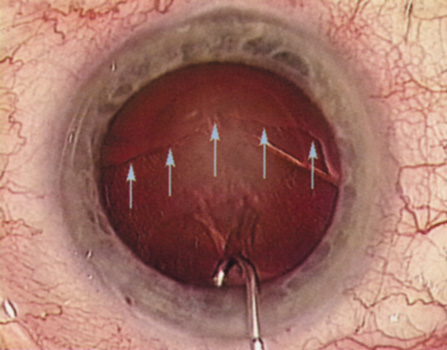

In some cases, corneal topography is an invaluable aid in surgical planning as well. In patients with high astigmatism, the topography can indicate the best meridian for placement of limbal relaxing incisions (Fig. 5). The topography also may be used to confirm the keratometric measurements.